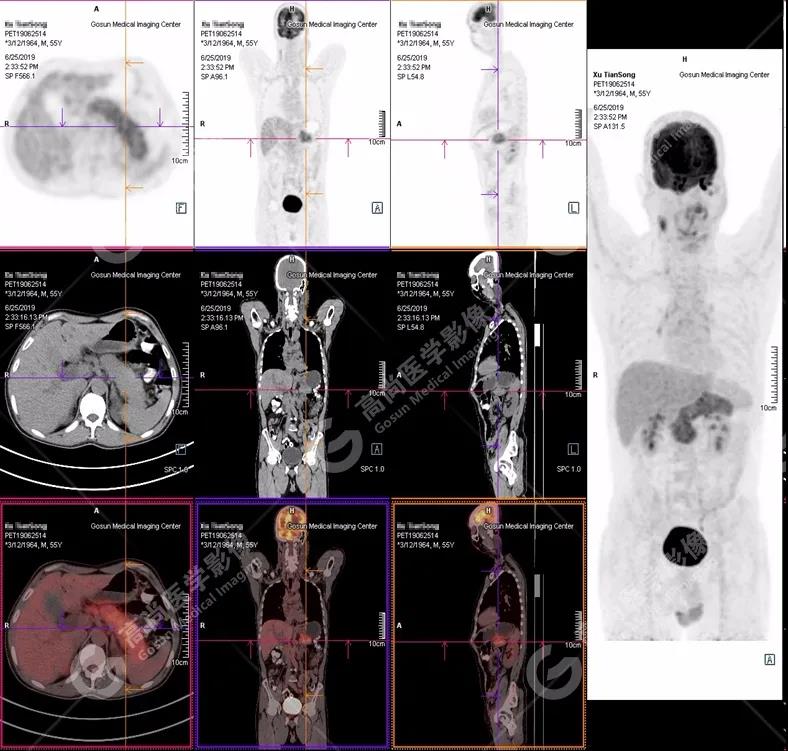

PET/CT 全身圖

胰腺腫脹、密度均勻,代謝彌漫性不均勻增高,SUV最大值5.2  平均值4.0

(1)胰腺輕度腫脹,胰腺體尾部胰管狹窄,未見(jiàn)明顯占位性病變,代謝彌漫性增高。

(2)胰周(胰胃間隙)稍大淋巴結(jié),代謝增高。

(3)全身其它部位未見(jiàn)明顯高代謝惡性腫瘤征象。